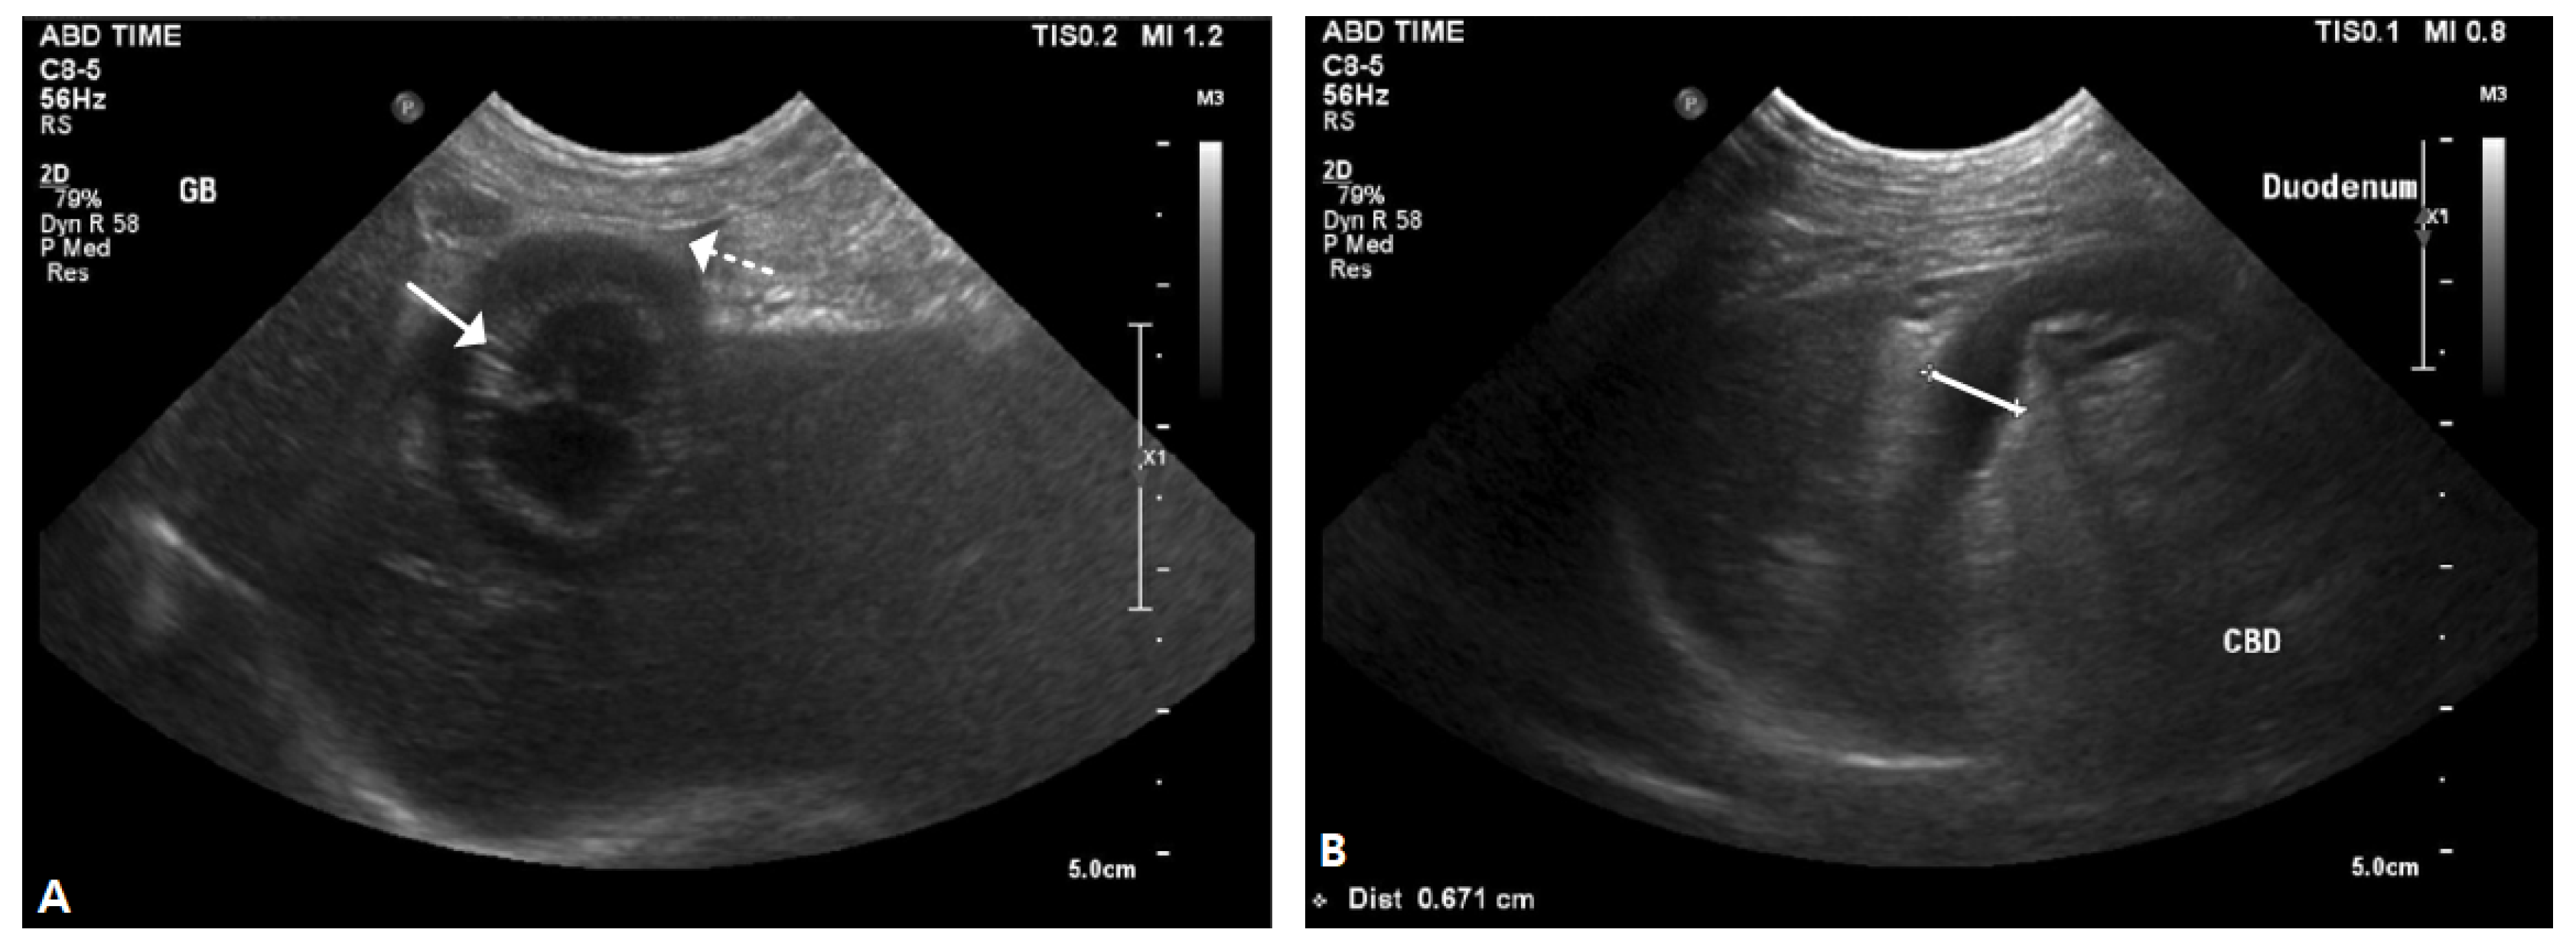

2.1. Case I